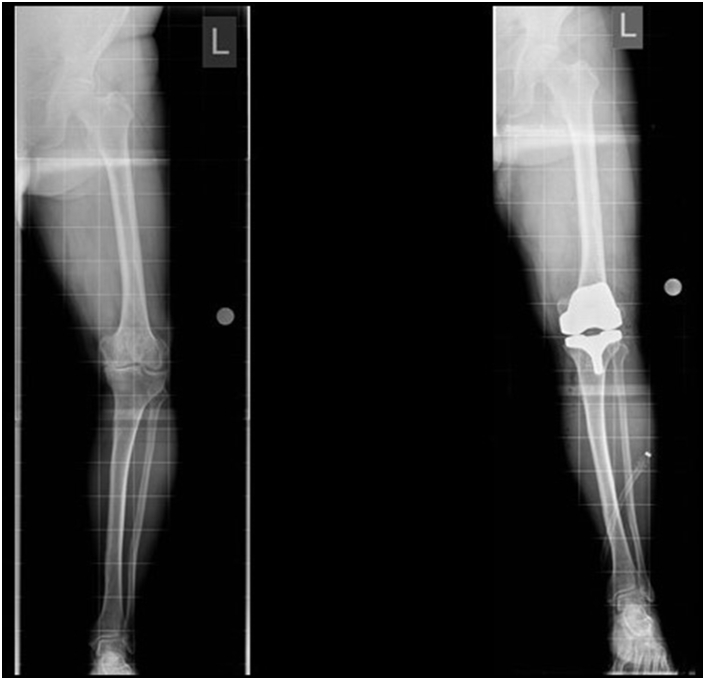

5.2. Single stage deformity correction & TKA

In this approach a corrective osteotomy is performed concomitantly with TKA as a single-stage procedure.30 In a malunited femur or tibia, corrective osteotomy is performed before TKA and fixed with an internal implant or a long stem prosthesis (Fig. 6A and B). Navigation assistance is recommended to achieve greater accuracy and because the metalwork may hinder the use of conventional TKA instrumentation.31

Fig. 6.

Single stage TKA with osteotomya - significant Valgus tibial deformity with Valgus OAb - single stage correction, osteotomy with long stem TKR.

The patient is spared multiple operations although recovery may be longer and more difficult compared with staged procedures.9 Blood loss and cement extrusion through the osteotomy site during implantation of TKA, with consequent non-union, can occur.

Lonner et al.5 reported 11 knees with extra-articular deformity treated by femoral osteotomy followed by TKA in a single setting. Although they reported significant improvements in the Knee Society Score, the complication rate was 45%. Madelaine et al.32 reported 4 major post-operative complications and 4 intra-operative tibial plateau fractures in their series of 15 knees of single-stage HTO and TKA. Although evidence is limited to small case series, the complication rate of this complex procedure appears to be high.